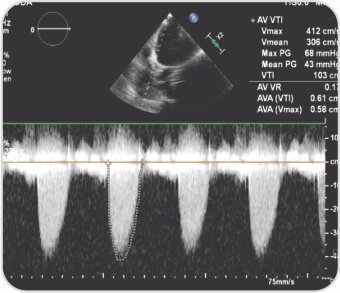

سيدة تبلغ من العمر 66 عامًا، تعاني من ارتفاع ضغط الدم، وتم تقييم ضيق التنفس الجهدي من الدرجة الثانية وتبين أنها مصابة بتضيق شديد في الأبهر، Sievers 0 bicuspid. كشف CAG عن الشرايين التاجية الطبيعية. تم إجراء عملية TAVI بنجاح تحت التخدير الواعي باستخدام جهاز Evolute R الممتد ذاتيًا مقاس 23 مم دون أي مضاعفات.